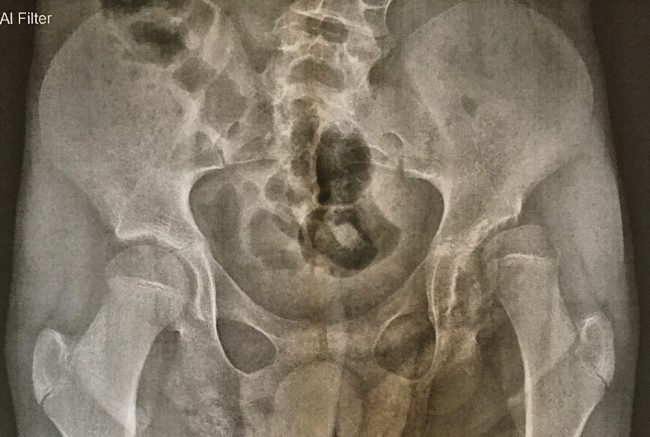

Fabian braucht 2018 Hüft-Operation

Beim Orthopädentermin im Juni hat es sich ja schon angedeutet, jetzt haben wir die Bestätigung durch die Klinik. Fabian wird 2018 eine ähnliche Hüftoperation brauchen, wie Jana letztes Jahr. Der Hüftkopf steht schon zu über 50% außerhalb der Hüftpfanne, was zum einen Schmerzen bereiten könnte und zum anderen in absehbarer Zeit seine Bewegung stark einschränkt.…